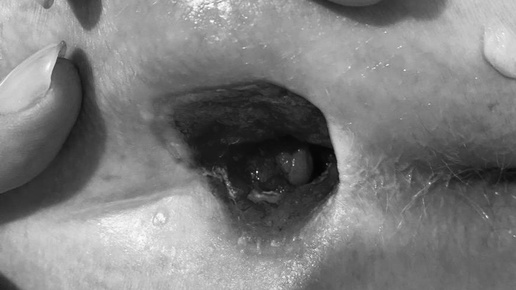

Как лечить пролежни? Часто лежачих больных выписывают домой из стационара с уже сформировавшимися пролежнями, причем, не снабдив родственников рекомендациями по уходу. Близкие пациента цепляются за разрозненные советы и непроверенную информацию, допуская одни и те же ошибки. В результате пролежни не заживают буквально годами. Давайте разберемся, как не допустить необратимых изменений. Я вижу на мумифицированной черной поверхности дорогую заживляющую сетку. Ее наложили и родственники больного. Приступаю к обработке, вздыхаю, и сетка летит в мусорный пакет...

Пролежни: фазы развития и методы лечения.

Это серьезная проблема для многих людей, особенно для тех, кто нуждается в длительном уходе и имеет ограниченную подвижность. Они могут быть очень болезненными и требуют немедленного вмешательства. В этой статье мы рассмотрим различные фазы развития пролежней и методы их лечения, чтобы помочь вам лучше понять эту проблему и обеспечить правильный уход за лежачими больными. Пролежни - это язвы, которые образуются на коже из-за длительного давления и трения. Они часто возникают у лежачих больных, людей с ограниченной подвижностью или с ослабленным иммунитетом...